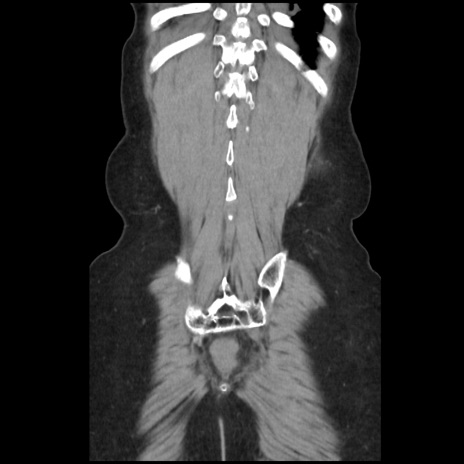

症例32(冠状断像)

横断像

【症例】40歳代 女性

【主訴】上腹部痛、嘔気・嘔吐

【現病歴】約9時間前頃から急に上腹部痛、嘔気、嘔吐が出現。改善しないため救急要請。

【既往歴】子宮頚癌(広汎子宮全摘術、放射線療法)、腸閉塞

【身体所見】腹部:平坦、軟、腸雑音亢進、上腹部を中心に腹部全体に圧痛あり。

【データ】WBC 8400、CRP 0.03